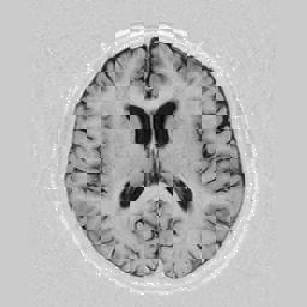

I later attempted 10 iterations at level 2, then 2 iterations at level 1, and 1 iteration at the finest level. Visual results can be seen in Figure [*].

Figure: Multi-scale NRR. From left to right, top then bottom: before NRR; after 10 iterations of NRR at level 2; after another 2 iterations of NRR at level 1; after 1 iteration at level 0.

Lastly, Figure [*] shows 10 iterations at level 2, 6 iterations at level 1, and 6 at level 0.

Figure: Multi-scale NRR. From left to right, top then bottom: before NRR; after 10 iterations of NRR at level 2; after another 6 iterations of NRR at level 1; after 6 more iterations at level 0.